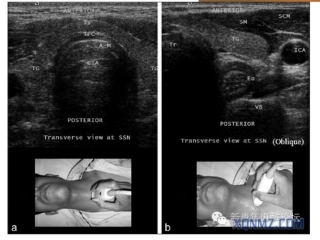

1最近几年超声在麻醉的应用可谓突飞猛进,如果在PubMed数据库中使用“Ultrasoundanesthesia”这个关键词来检索,可以检索到8000多篇文献。...